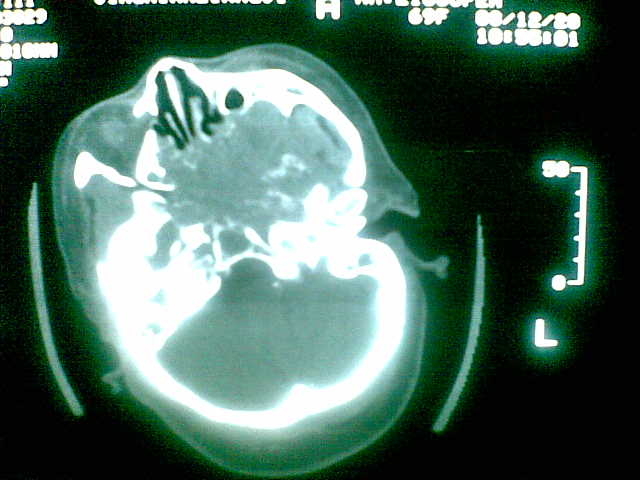

69岁 女 主因头痛就诊。大家看看起源于哪里啊

颅底骨质破坏伴软组织密度影、斑片状高密度(死骨影)。

考虑:脊索瘤。